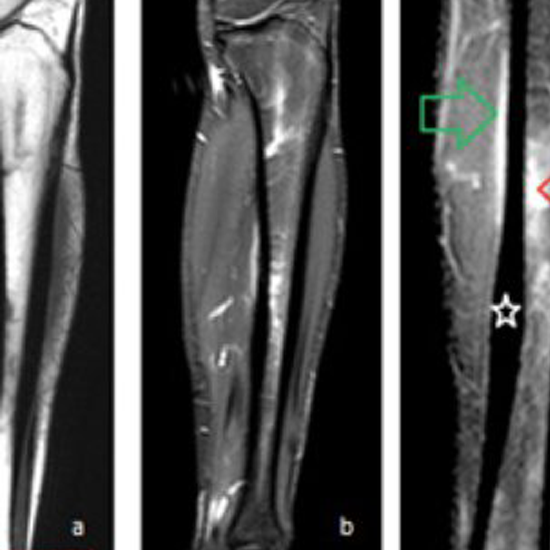

NCCT Right Tibia is a plain scan to visualize the bone (tibia) along with the surrounding soft tissues like the cartilage, tendons, ligaments, muscles, and blood vessels.

NCCT (non-contrast computed tomography) screening of the Right Tibia is a non-invasive radiology test used to evaluate the condition of the Right Tibia and surrounding tissue. NCCT Right Tibia is done to look for the conditions of the Right Tibia and the surrounding area.